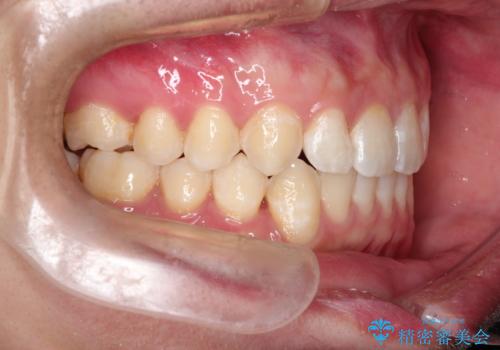

前歯がガタガタ インビザラインによる矯正

- 前歯がガタガタ、下の犬歯が飛び出ているのを主訴に来院されました。

下の奥歯を後方へ移動させてスペースを確保して、前歯を並べる計画としました。

目立たない装置をご希望されたので、インビザラインにて矯正治療を行いました。